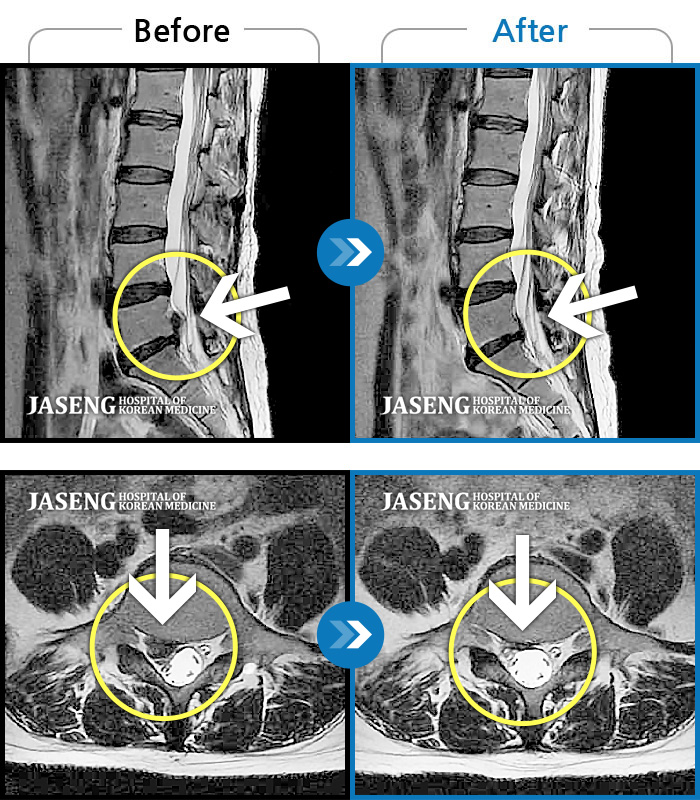

허리디스크

수원 · 김태성 원장

우측 허리 통증과 우측 다리 방사통으로 활동하기 힘든 상태

촬영시기

2021.02.03 ~ 2021.07.09

2022.03.25